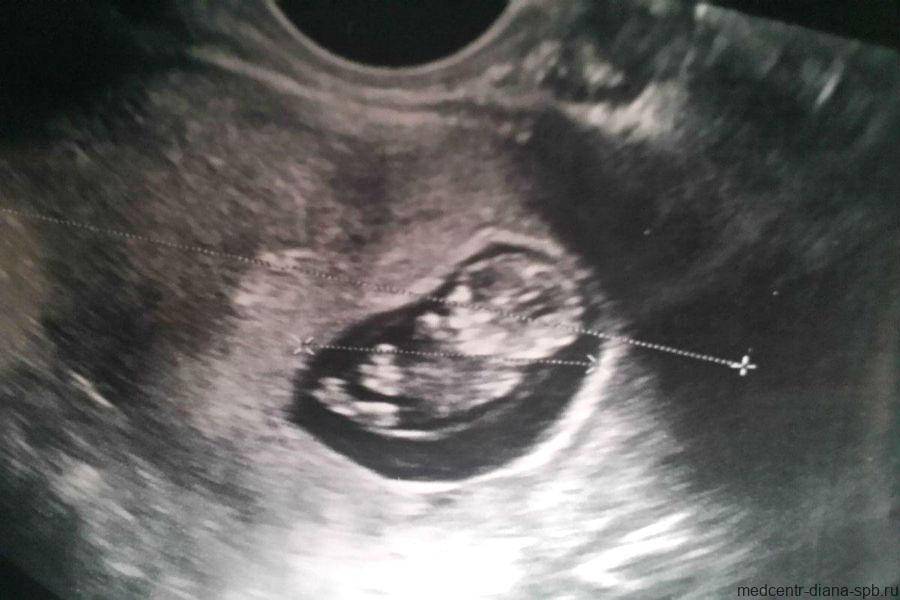

Фото УЗИ ребенка на 9 неделе беременности

В этот период происходит активное формирование структур мозга, в частности гипофиза и мозжечка. Нижние и верхние конечности удлиняются, у малыша появляются почки и печень. Также идет закладка черт лица. Пол ребенка еще не определяется, однако в организме плода начинают вырабатываться половые клетки – яйцеклетки у девочек и предшественники сперматозоидов у мальчиков. Размеры плода можно сравнить с размерами крупной вишни.

На УЗИ врач четко видит многоплодную беременность, а также определяет место прикрепления плодов. Сердцебиение хорошо прослушивается. На снимке не видны патологии и пол ребенка.